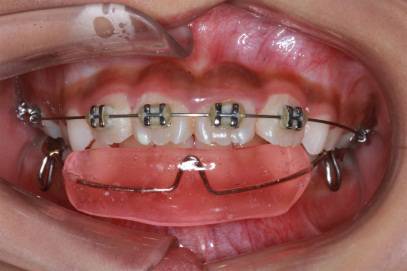

放射检查:一般包括X线头影测量片、曲面体层片和CBCT(锥束CT)。有时还包括其他放射检查,比如螺旋CT等。通过放射检查,医生可以看到骨骼及牙齿的形态、位置及发育状况,以及是否有牙体、根尖周、牙周疾病等,从而评估是否需要正畸治疗、进行何种治疗。

头影测量片(上)、曲面体层片(中)和锥束CT(下)